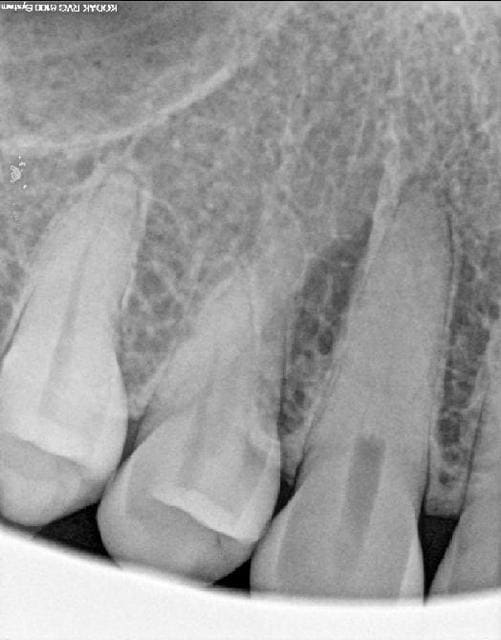

Patiente de 30 ans, hygiène parfaite se plaint de douleurs intermittentes au niveau incisivo-canin supérieur droit depuis quelque jours. La douleur monte puis se calme.

Percussion et palpation vestibulaire douloureuse sur 13.

Couronne de la 13 indemne de restaurations ou caries.

Test au froid négatif (la douleur débute dès le retrait de la boulette réfrigérée)

Tes de morsure négatif.

Sondage normal. Gencive belle, légère récession gingivale.

Radio ci jointe.

Elle a eu un accident de voiture y a 2 semaines mais sans choc au visage ou sur les dents selon elle.

Ben elle est complètement calcifiée, ta 13!

Dégénérescence calcique, ça me paraît cohérent avec les symptomes...

Euhhh, il n'y a pas une fracture au tier moyen?

L'image apicale me dit qu'il faut traiter la racine.

Le test de morsure négatif me fait écarter la fracture.

D'aprés mon avis, la 13 nécessite un traitement endodontique..

Je soupconne cette dent d'avoir deux canaux, de plus, meriterait une 3D, pour justement infirmer la fracture.